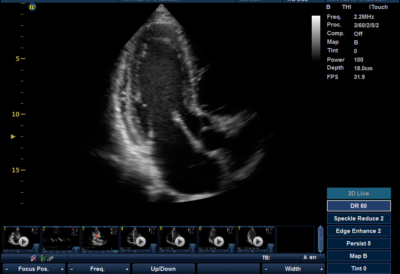

The Lambda P9 is a shared services system capable of producing excellent cardiac echo and general ultrasound images. With a highly adaptable ergonomic cart, the P9 delivers the same capability and versatility as a cart based system with many advanced imaging features to maximize utility and productivity while maintaining excellent value and return on investment.

Whale’s proprietary HD Doppler provides excellent color range and sensitivity without compromising frame rate. Other Advanced imaging features such as tissue harmonics, compound imaging, contrast enhancement and speckle reduction help to ensure image quality is crisp, clear and optimized.

Clinical Images